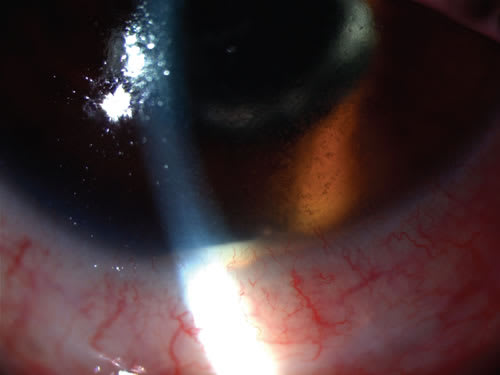

Uveitis refers to inflammation of the uveal coat of the eye and is a prevalent cause of visual impairment in most countries. The uvea consists of 3 tissues that are continuous with each other: the iris anteriorly, the choroid posteriorly, and the ciliary body between the iris and choroid. In addition to providing most of the blood supply of the intraocular structures, the uveal coat acts as a conduit for immune cells, particularly lymphocytes, to enter the eye. Consequently, it is directly involved in many intraocular inflammatory processes. The International Uveitis Study Group classifies uveitis in terms of eye(s) involved (ie, unilateral or bilateral), course (ie, acute [lasting less than 12 weeks] or chronic [lasting more than 12 weeks]), and anatomical location in the eye (Table 1).1 Anterior uveitis includes iritis, anterior cyclitis, and iridocyclitis involving the iris and/or pars plicata (anterior ciliary body). Intermediate uveitis includes pars planitis, posterior cyclitis, hyalitis, and basal retinochoroiditis, referring to inflammation of the pars plana (posterior ciliary body) and/or adjacent peripheral retina. Posterior uveitis includes focal, multifocal, or diffuse choroiditis; retinitis; retinochoroiditis; and chorioretinitis; the latter 2 terms indicate which tissue appears primarily involved. Panuveitis refers to inflammation that involves both the anterior and posterior segments. Uveitis is further classified on the presence or absence of granulomatous inflammation, marked by “mutton fat” keratic precipitates (large, greasy-appearing collections of inflammatory cells on the corneal endothelium), iris nodules, and/or choroidal granulomas (Figure 1). Uveitis frequently occurs in the context of systemic inflammatory disease, which may cause additional morbidity. Conversely, uveitis often represents the first manifestation of a systemic disease (Figure 2).2,3 Sixty percent of uveitis is limited to the eyes; in the other 40% of patients, an underlying systemic disease, often of autoimmune origin, can be identified.4 Consequently, management of patients